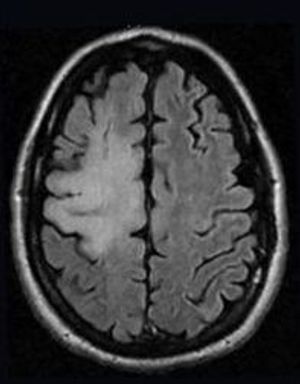

A Case of PML-IRIS: Diagnostic and Treatment Considerations

ByElizabeth A. Mills, PhD,Yang Mao-Draayer, MD, PhD

On the challenges of treating progressive multifocal leukoencephalopathy in MS patients.